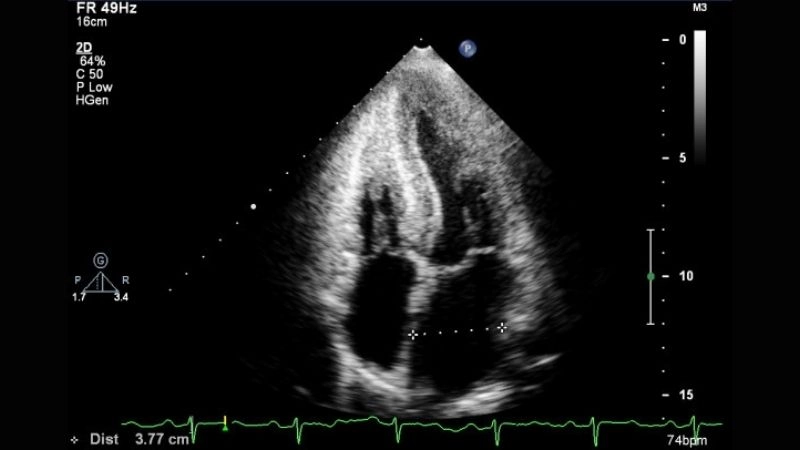

Images visual examples of Amyloid Cardiomyopathy

Visual examples of Amyloid Cardiomyopathy often highlight thickened heart walls caused by amyloid deposits, showing reduced flexibility, impaired pumping function, and fluid accumulation in surrounding tissues.